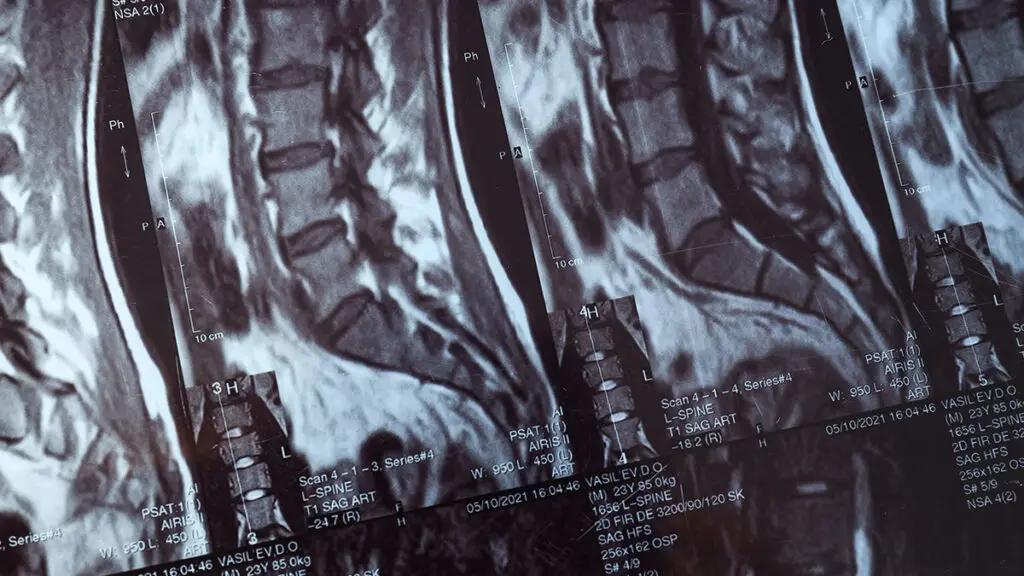

Global Spine Solutions è il centro di riferimento a Roma per chi cerca un specialista tumori sistema nervoso con competenze di alto livello in neurochirurgia spinale mininvasiva. Il nostro team multidisciplinare accompagna ogni paziente dalla diagnosi al trattamento, con un approccio personalizzato che integra le tecnologie più avanzate nel campo delle patologie vertebrali e neurologiche.

Affidarsi al giusto specialista tumori sistema nervoso fa la differenza. Da Global Spine Solutions trovi professionisti con esperienza pluriennale nelle patologie della colonna vertebrale, capaci di valutare ogni caso in modo accurato e proporre il percorso terapeutico più adeguato, privilegiando ove possibile le soluzioni conservative e mininvasive rispetto alla chirurgia tradizionale.

Il team di Global Spine Solutions è a tua disposizione per una valutazione clinica approfondita se stai cercando un specialista tumori sistema nervoso di fiducia. I nostri professionisti ti seguiranno in ogni fase: dalla diagnosi all'eventuale intervento, fino al recupero funzionale completo.